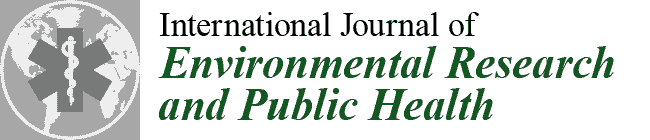

2. Materials and Methods

2.1. Subjects and Study Design